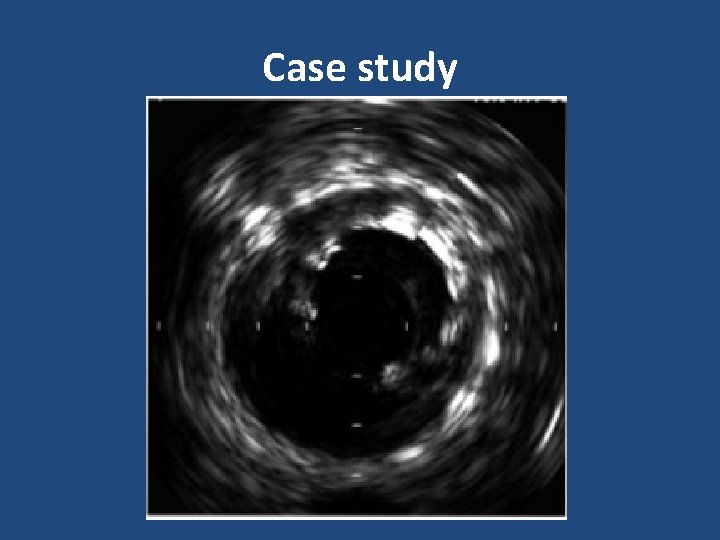

Case study